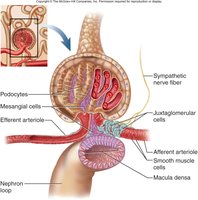

The JGA is a specialized structure where the distal tubule contacts the afferent arteriole. It regulates blood pressure and filtration rate.

Granular (JG) Cells: Detect blood pressure changes and release renin when BP is low.

Macula Densa: Detects filtrate osmolarity and signals adjustments in arteriole diameter.

Mesangial Cells: Release paracrine signals to regulate glomerular filtration.